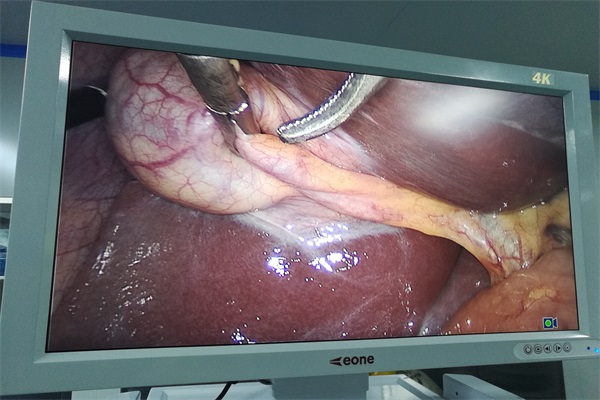

內窺鏡監視器微創醫療器械是臨床醫學與近年來迅速發展的生物工程、光學、精密制造、圖像處理、醫用材料、光機電信息等高科技學科的有機結合體。內窺鏡監視器通過成像系統對體內器官進行臨床診斷,并利用微創手術器械進行微創診斷。

隨著居民生活水平的提高和健康意識的覺醒,更加注重疾病診治的及時性、準確性、低風險性和術后恢復能力,內窺鏡監視器微創診療憑借診療準確性高,創口小,不易感染,術后恢復快、近乎無痕跡等特點受到醫學界的廣泛關注。截至2012年,衛計委已組織建立”內鏡與微創醫學培訓基地”400余家,用于內鏡醫師的技能培訓與考核,加強了醫師人才隊伍建設,提高了臨床應用水平,目前,我國約90%的醫療機構已開展內窺鏡下微創診療項目,內窺鏡監視器微創醫療器械正在耳鼻喉科、外科、婦科等各個科室得到推廣應用。